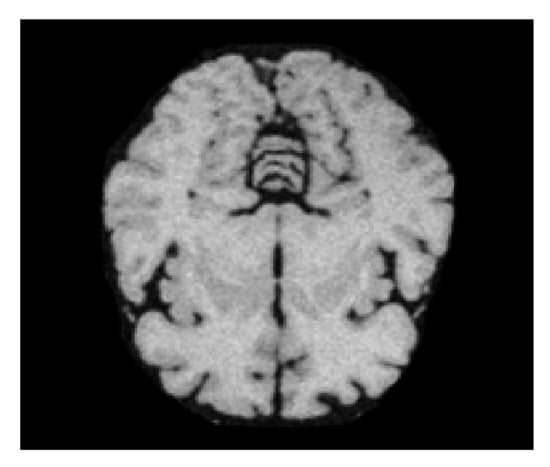

The ultimate objective of this research study is to apply a mask over the detected brain for segmentation purposes. We masked the segmented part using the sigmoid function on each pixel of the detected brain. The convolutional network generates masks from positive regions already selected by the ROI classifier. We had already created ground truth in earlier stages of experiments; therefore, the system predicted applying a mask using a low resolution of 28 × 28 to ensure the minimum memory usage. The low pixel resolution of the masked image shows its lighter layer. Therefore, we scaled down the ground truth ROI to 28 × 28 while padding it with 0 to avoid distortion or disruption. After predicting overlay masks, we scaled their resolution up for inference purposes. The targeted region, the skull-stripped brain, exists under an overlay mask. Finally, we have concluded that the skull stripping from brain MR images using a deep learning technique of Mask–RCNN. Figure 12 depicts the output of the ground truth mask and predicted mask over the brain, while Figure 13 shows a skull-stripped brain MR image.

Figure 13. Skull-stripped brain MR Image.